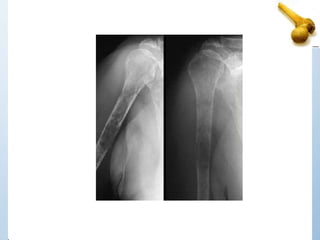

AGE 13

Location Metadiaphysis

Margins 1A-1B

Periosteal reaction none

Matrix None

other Trabecular struts

DX UBC